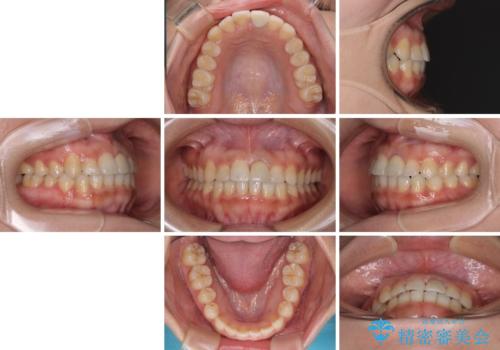

前歯のクロスバイトと変色した歯 ワイヤー矯正とセラミック治療

- 前歯のクロスバイトと神経を取り除いた後に変色してしまった前歯を気にして来院された患者様です。

ワイヤー矯正により矯正治療を行った後に、前歯の補綴治療を行うこととしました。

変色してしまった前歯は、反対側の歯と比べて歯肉が覆い被さっていたため、骨整形を含めた歯周外科処置を行い、歯肉ラインを整えることとしました。

歯周外科処置を行うかどうかは非常に悩んでいらっしゃいましたが、範囲がそれほど広くないため術後の痛みも強くないだろうということで、処置を行うこととなりました。